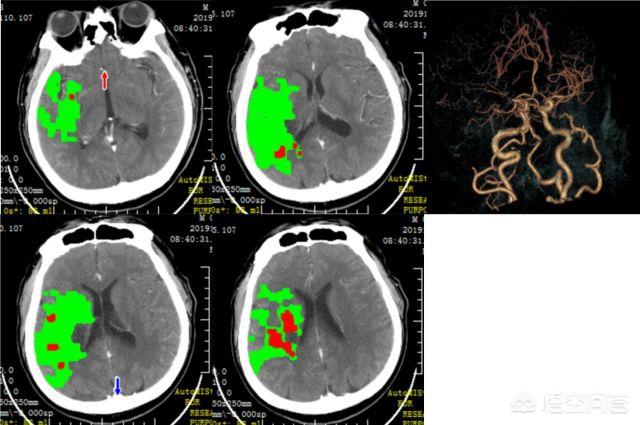

Le traitement de l'infarctus cérébral peut être divisé en phases aiguës et chroniques. Dans la phase suraiguë de l'infarctus cérébral, ou accident vasculaire cérébral ischémique, nous pouvons généralement procéder à une thrombolyse intraveineuse ou à une thrombolyse par cathéter artériel. Si la fenêtre temporelle pour la thrombolyse intraveineuse ou le cathétérisme artériel est dépassée, nous prenons généralement des médicaments généraux, souvent appelés vasodilatation, activation de la stase sanguine et thérapie antiplaquettaire. Un mois après l'infarctus cérébral, nous pouvons effectuer une angiographie cérébrale et s'il s'avère que l'infarctus cérébral est causé par une sténose cérébrale, certains patients peuvent bénéficier d'un traitement par endoprothèse.

Le facteur de risque de l'infarctus cérébral au stade de l'attaque aiguë est extrêmement élevé, s'il n'y a pas de traitement de secours en temps utile, le risque de décès est très élevé, le plus vite sera le mieux, le traitement à ce moment-là est principalement basé sur la thrombolyse, l'extraction du thrombus, l'intervention, l'objectif étant de recanaliser rapidement les vaisseaux sanguins.

1. ultra-précoce

Cela signifie que dans les 3 à 4,5 heures, les cellules nerveuses du cerveau ne sont pas complètement mortes à cause de l'ischémie, pas plus de 3 à 4,5 heures, (s'il s'agit d'un début nocturne, en comptant à partir du moment où il s'est endormi), vous pouvez utiliser la thrombolyse. L'effet est meilleur. Des résultats immédiats peuvent être obtenus.

2. phase aiguë

Au stade aigu du traitement, il n'y a pas de médicament spécifique disponible, et la récupération de la fonction du membre est relativement lente, car elle dépend principalement de la compensation de la fonction nerveuse. À ce stade, le traitement consiste principalement à prévenir l'expansion et la récurrence du thrombus, à éliminer les conditions propices à la croissance du thrombus et à favoriser la fonte du thrombus. Maximiser la protection des cellules nerveuses du cerveau qui sont endommagées par l'ischémie mais qui ne sont pas mortes. Les médicaments et la chirurgie sont utilisés en fonction de l'état du patient.